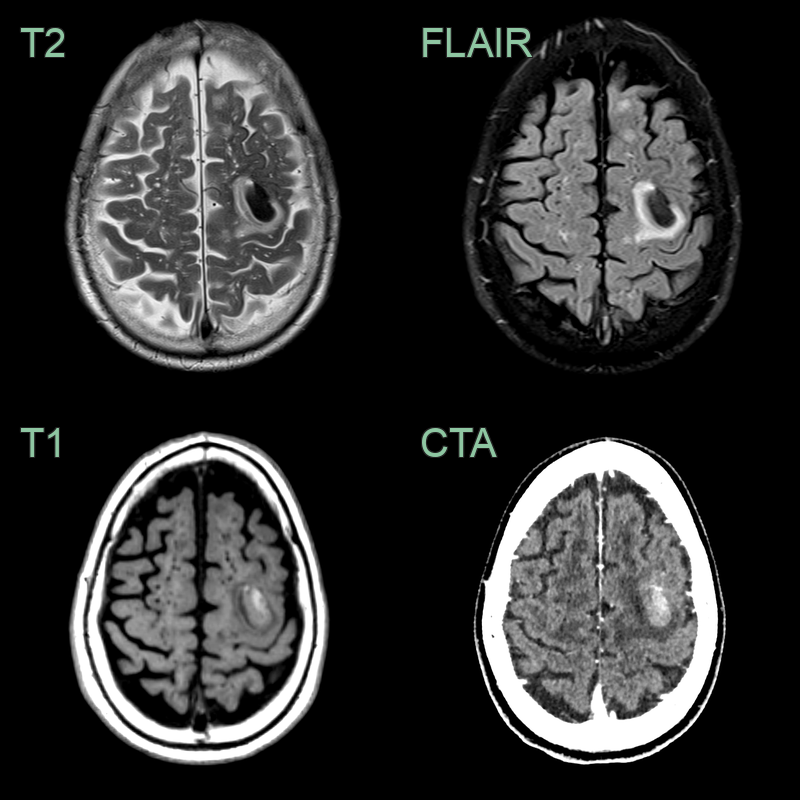

• 75-year-old patient presented with affecting right arm weakness.

• The initial MRI showed a lobar hemorrhage affecting the left precentral gyrus. There was a multi-plot pattern of (posterior-predominant) small vessel disease, many enlarged subcortical perivasular spaces, and extensive superfial siderosis but only a few few lobar microhemorrhages.